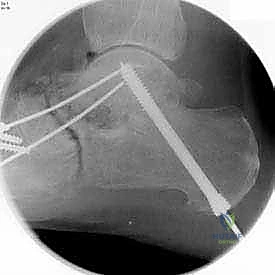

بعد التأكد من الوضعية المثالية للعظام، يتم تثبيتها بقوة باستخدام مسامير معدنية مجوفة من التيتانيوم (Cannulated Screws) أو شرائح معدنية خاصة. يتم إدخال المسامير تحت توجيه الأشعة السينية المباشرة (Fluoroscopy) داخل غرفة العمليات لضمان الدقة المتناهية. هذه المسامير تضغط العظام معاً وتمنع أي حركة حتى يحدث الالتئام التام.